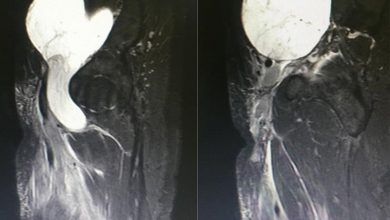

استئصال ورم يزن 1 كجم من حوض أربعيني بمستشفى سليمان الحبيب بالقصيم

تمكّن فريق طبي بمستشفى الدكتور سليمان الحبيب بالقصيم، من استئصال ورم يزن 1 كجم من الفخذ الأيسر لمريض يبلغ من…